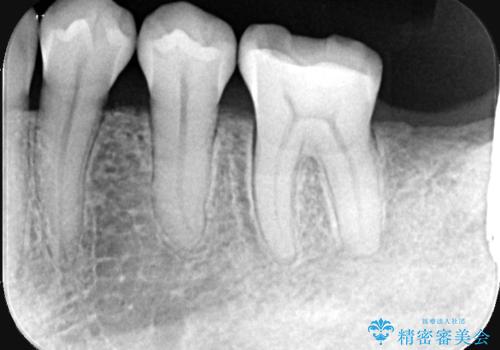

- 左下6番目(第一大臼歯)の詰め物が欠けたことを主訴にご来院されました。

診査の結果、過去に施されたCR(コンポジットレジン:プラスチックの詰め物)による修復範囲が非常に広く、咬合圧に耐えきれずに破損している状態でした。第一大臼歯は噛み合わせの要となる歯であり、最も強い力がかかるため、部分的な詰め物による再修復では再び欠けたり、残っている自分の歯まで割れてしまったりするリスクが高いと判断。歯全体を強固に保護し、機能性と耐久性を確保するために、セラミッククラウンによる修復計画を立案しました。

治療では、破損した古いレジンを除去し、セラミッククラウンを装着するための形を整えました。

広範囲にわたる欠損をセラミッククラウンで覆うことにより、咬合時の負担が歯の一部に集中するのを防ぎ、歯根の破折リスクを大幅に軽減させています。精密に作製されたセラミックは適合性に優れており、歯との段差がほとんどないため、細菌が入り込みにくい清潔な状態を作ることができます。